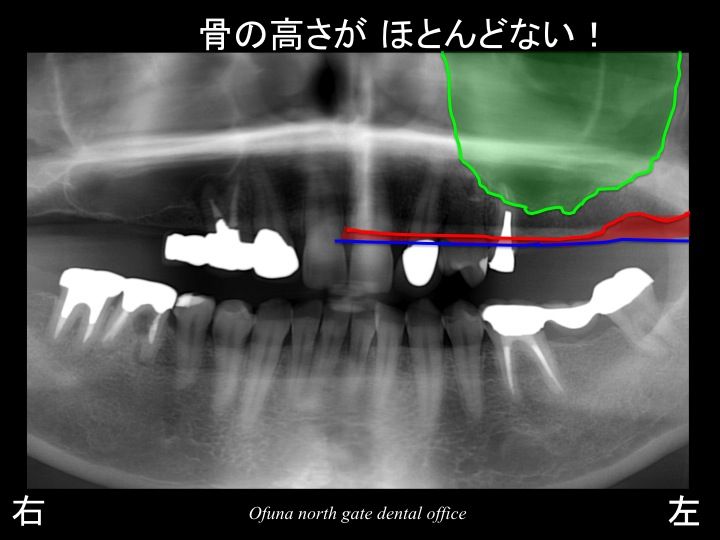

今回治療を行う部位は上顎左側です。

上顎左側の奥歯が2歯分欠損しています。

いつものように 骨吸収の状態を分かりやすくするために

骨吸収の状態を線で書いたのが以下のレントゲンになります。

青線が骨吸収を起こす前の骨の位置です。

赤線は、現在の骨の位置です。

次に上顎洞という空洞を見てみましょう!

以下のレントゲンの緑線は上顎洞という空洞です。

骨ではなく、穴が開いているのです。

さらに分かりやすくするために上顎洞を緑色で塗ってみましょう!

骨の高さが非常に少なくなっています。

このままであるとインプラント治療は難しくなります。

短いインプラントしか埋入するこができません。

しかし、今回の症例では、4〜5ミリ程度の骨の高さしか存在していません。

これは、難症例と言えます。